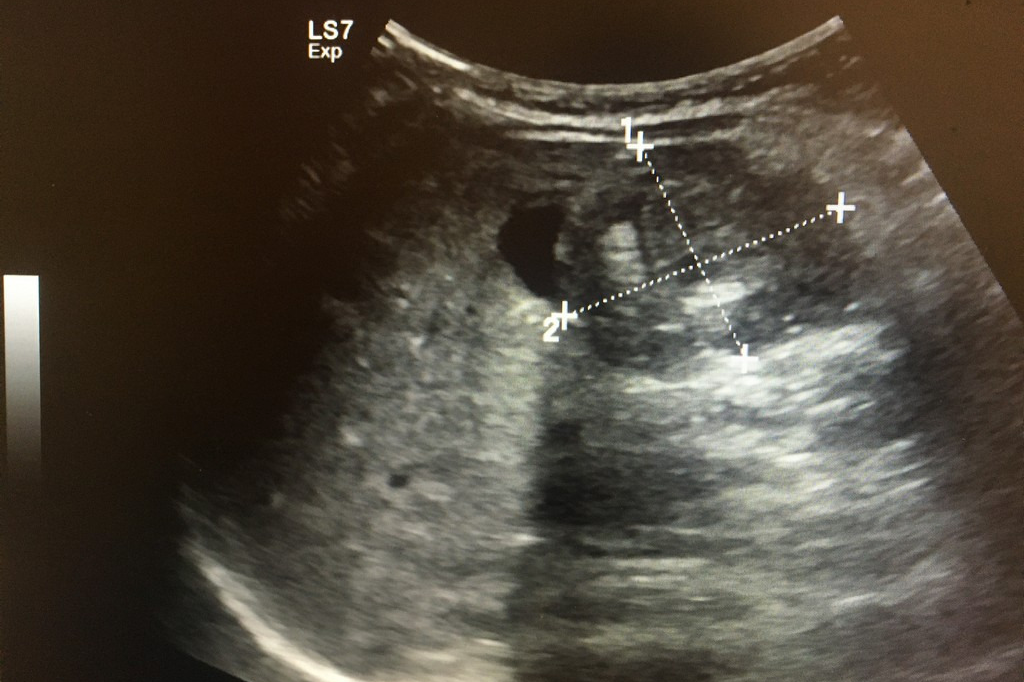

복부 초음파는 초음파(ultrasound)를 이용해 복부 내 장기들의 상태를 확인하는 비침습적 검사 방법입니다. 방사선을 사용하지 않아 인체에 해롭지 않고, 고통 없이 실시간으로 복부 장기들을 관찰할 수 있다는 점에서 가장 기본적이면서도 효과적인 진단도구로 평가받습니다.

초음파 탐촉자(Probe)에서 발생한 고주파 음파가 인체 내부 장기에 부딪혀 반사되며, 복부 초음파로 알 수 있는 것은 바로 이 반사파를 영상화해 간, 담낭, 췌장, 비장, 신장(콩팥), 방광, 대동맥, 림프절 등의 상태를 분석하게 됩니다.